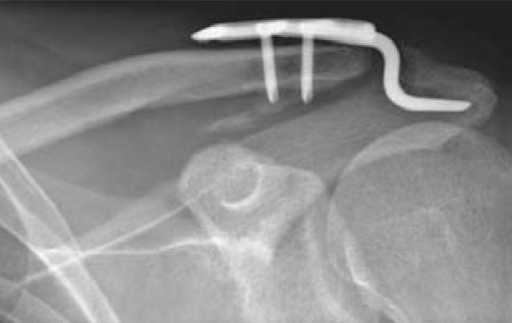

Недавно наткнулся на такого рода "новшество" - пластинка от АО для фиксации разрывов акромеально-ключичных сочленений.

Детальнее по ссылке

фото приложил.